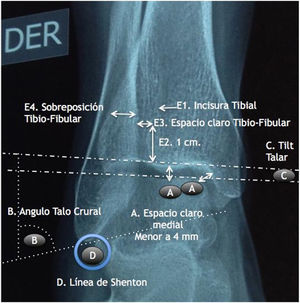

Materiales y MétodosSe realizó un ensayo auto-controlado, aleatorizado, doble ciego, multicéntrico, mediante la aplicación de encuestas en tres países a ortopedistas generales, subespecialistas en cirugía de pie y tobillo y residentes de ortopedia y traumatología. Se estableció el criterio de aleatorización simple mediante la presencia de los encuestados en los simposios de pie y tobillo en la ciudad de Guayaquil en el marco del congreso Ecuatoriano de Ortopedia y Traumatología, En la ciudad de Cali en el marco del curso nacional del Pie y Tobillo de la sociedad Colombiana de Cirugía Ortopédica y Traumatología y en la ciudad de Cancún en el marco del Congreso mexicano de Ortopedia y Traumatología de la FEMECOT, estableciéndose como criterio de inclusión estar en disposición de evaluar los casos clínicos y realizar la encuesta independientemente de su grado de entrenamiento o años de experiencia. Se entregaron cuatro casos de fracturas de tobillo Webber B de características quirúrgicas por sus mediciones radiológicas con desenlaces conocidos por los autores Senior (Eduardo Reina, Juan Manuel Herrera, Carlos Ramirez, Bosco Mendoza y Victor Toledo) como se observa en la figura 1.

En el caso número 1 se estableció como criterio quirúrgico la diferencia de el ángulo talocrural de 6° y la línea de shenton con una incongruencia de 3mm en el lado fracturado figuras 2 y 3

En el caso 2 se estableció como criterio quirúrgico el espacio claro medial aumentado de 5mm y la diferencia de 5 grados de el ángulo talocrural como se observo en las figuras 4 y 5,

En el caso 3 se estableció como criterio quirúrgico 1mm de discrepancia de la línea de shenton y una apertura de el espacio claro medial de 6mm, además de una malrotacion del peroné y discrepancia de el ángulo talocrural, como se observo en las figuras 6 y 7. figura 8, figura 9

En el caso 4 se estableció el criterio quirúrgico la diferencia de 9 grados en el ángulo talocrural con la radiografia comparativa y el espacio claro medial aumentado 1mm.